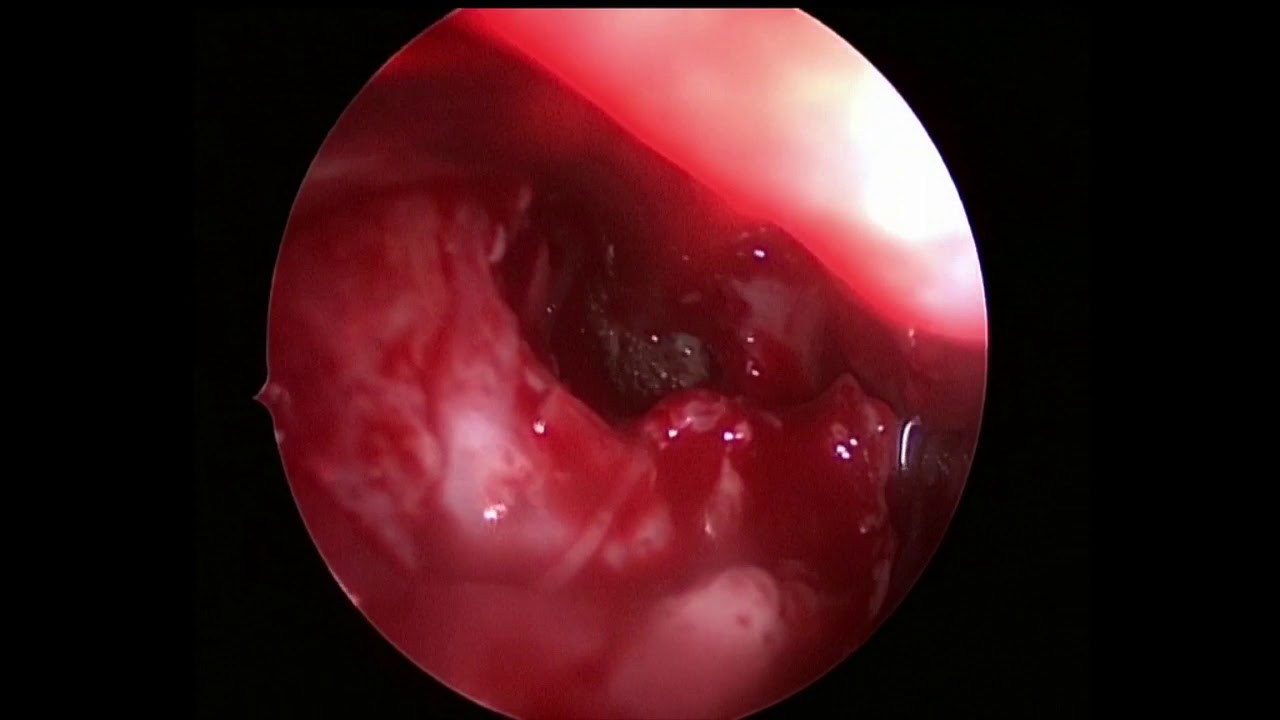

Эндоскопическая картина после операции. Под контролем оптики удалены несколько клеток решетчатой кости под средней раковиной, что позволило открыть соустья воспалённой гайморовой пазухи (большая стрелка) и других решёток (маленькие стрелки). Новые соустья широкие, гной из них не выделяется, пациент излечен.